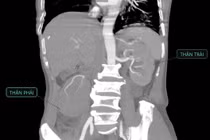

Suy gan cấp do viêm gan B là tình trạng gan bị tổn thương nghiêm trọng và mất chức năng đột ngột. Bệnh nhân phải đối mặt với những biến chứng nguy hiểm đe dọa tính mạng.